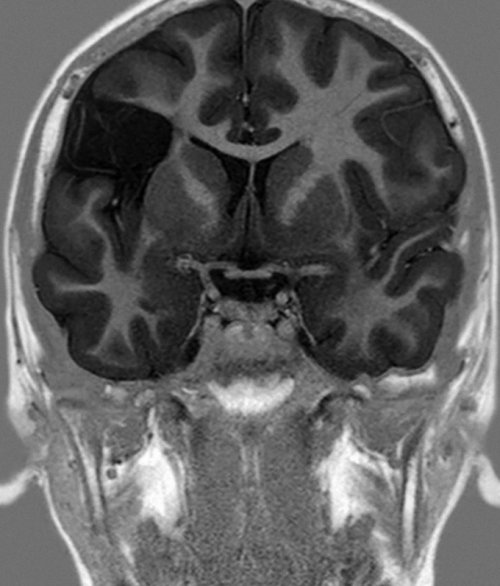

года (от 5 лет были разделены на Рис. 2. Больная И., 13 лет. МРТ. Глиоз медиобазальных отделов

правых конечностях, ощущения стягивания мышц | выявлены кистозно-атрофические изменения височно-инсулярной зоны, у 1 — кавернома островка (рис. 1, 2) | |